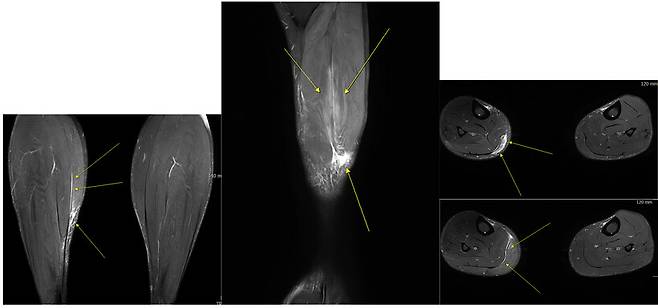

“어? 종아리 다쳤다면서? 난 3주 만에 운동했는데? 6주 걸린대? 잘못 본거 아니야?” 이런 얘기를 이미 들어 보셨을 수도 있고, 주위에서 경험해 본 적도 있을 것입니다. 종아리 근육 부상은 초음파를 통해서 진단이 가능하고, 파열의 기준까지 나눌 수 있기 때문에, 회복 및 복귀 기준에 대해서 보다 세밀하고 정확한 기준을 제시해 줄 수 있습니다.

때때로 MRI 검사를 필수로 하는 경우도 볼 수 있는데, 사실 초음파만으로도 정확한 진단 및 복귀에 대한 기준을 제시할 수 있고, 운동으로 복귀 전 MRI를 검사하는 것 또한 반드시 필요한 사항이 아닙니다. 종아리 근육이 파열되었을 때 진단에 대한 검사 방법, 진단의 분류, 운동으로 복귀하기 위해 필요한 시간 등에 대한 대략적인 설명을 드렸습니다.